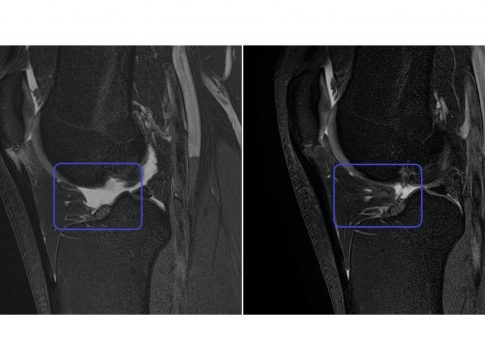

Por su parte, el segundo grupo se trató con una solución de PRP (Plasma Rico en Plaquetas), es decir, se obtuvo sangre periférica que fue centrifugada y aplicada siguiendo el mismo procedimiento. Ambos grupos siguieron tratamiento ambulatorio, sin ingreso hospitalario, y los resultados fueron medidos a nivel clínico con las escalas EVA y VISA-P y a nivel de imagen por ecografías, UTC y Resonancia Magnética 3 Tesla (alta resolución).

A los 6 meses, el grupo tratado con células madre mesenquimales cultivadas mostró por primera vez la restauración de la estructura del tendón hasta recuperar un 40% de la lesión en el 100% de los pacientes, mientras que el grupo tratado con PRP no mostró ni evolución ni regeneración y acabaron recayendo de su lesión.